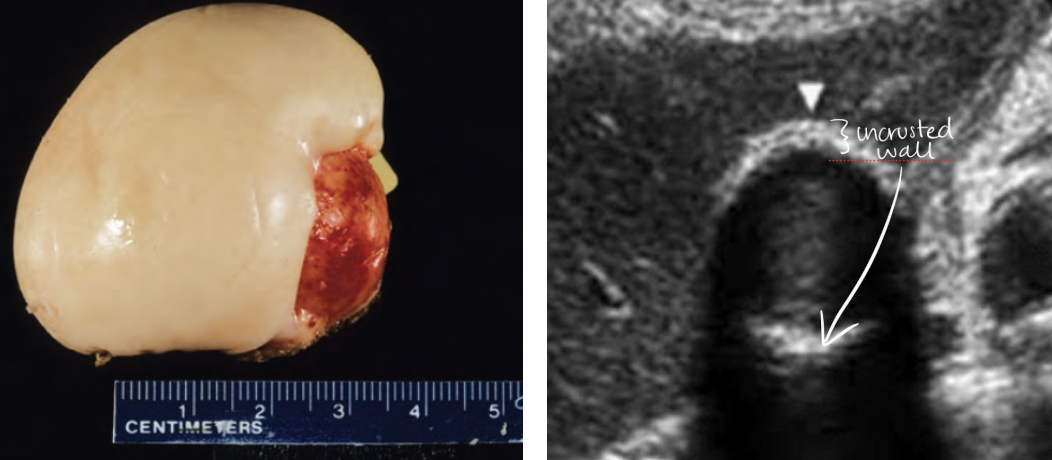

porcelain gallbladder

calcium incrustation of GB wall

rare occurrence

associated with gallstones

MC in elderly female

increased risk of GB carcinoma

differential dx: WES sign

SONO: porcelain gallbladder

bright echogenic echo in region of GB with posterior shadowing

GB wall thickly calcified with shadowing

Calcification may not include entire GB wall

??